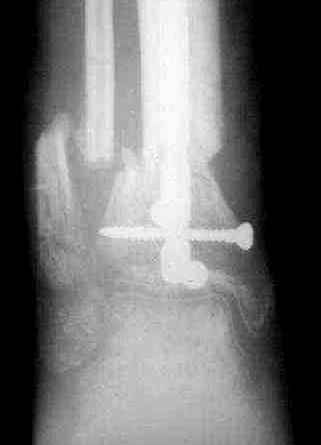

4. Никто не назвал методику, которая мне представляется наиболее удачной - тибиализация малоберцовой кости. Пластинку, конечно, придется убрать. Нужно наложить кольцевой Илизаров,

томировать малоберцовку на уровне дефекта, закрыто пересечь большеберцовую кость у основания острого края проксимального отломка - и подтянуть фрагмент малоберцовой кости в зону дефекта большеберцовой спицами с упорными площадками. Не обязательно при этом выводить строго в центр, достаточно сращения при боковом касании отломков - малоберцовая кость оттеснит как раз "сосульку" в сторону, и томированные края берцовых костей срастутся между собой. Есть еще ряд нюансов - готов расписать со схемами в случае, если будет принято решение в пользу этой методики.

Реализовал описанную выше методику, и в итоге вот что получилось. Высылаю лишь прямые проекции,

в боковых тоже всё в тему.

Очень пригодились карбоновые кольца (Джолдас -огромное спасибо, я твой должник!!!), поскольку остеопороз дистального отломка был просто невероятный. На цифровом рентгене с трудом угадывались контуры.

Рентген в процессе перемещения - внизу карбоновые кольца, тракция фрагмента спицами с упором.